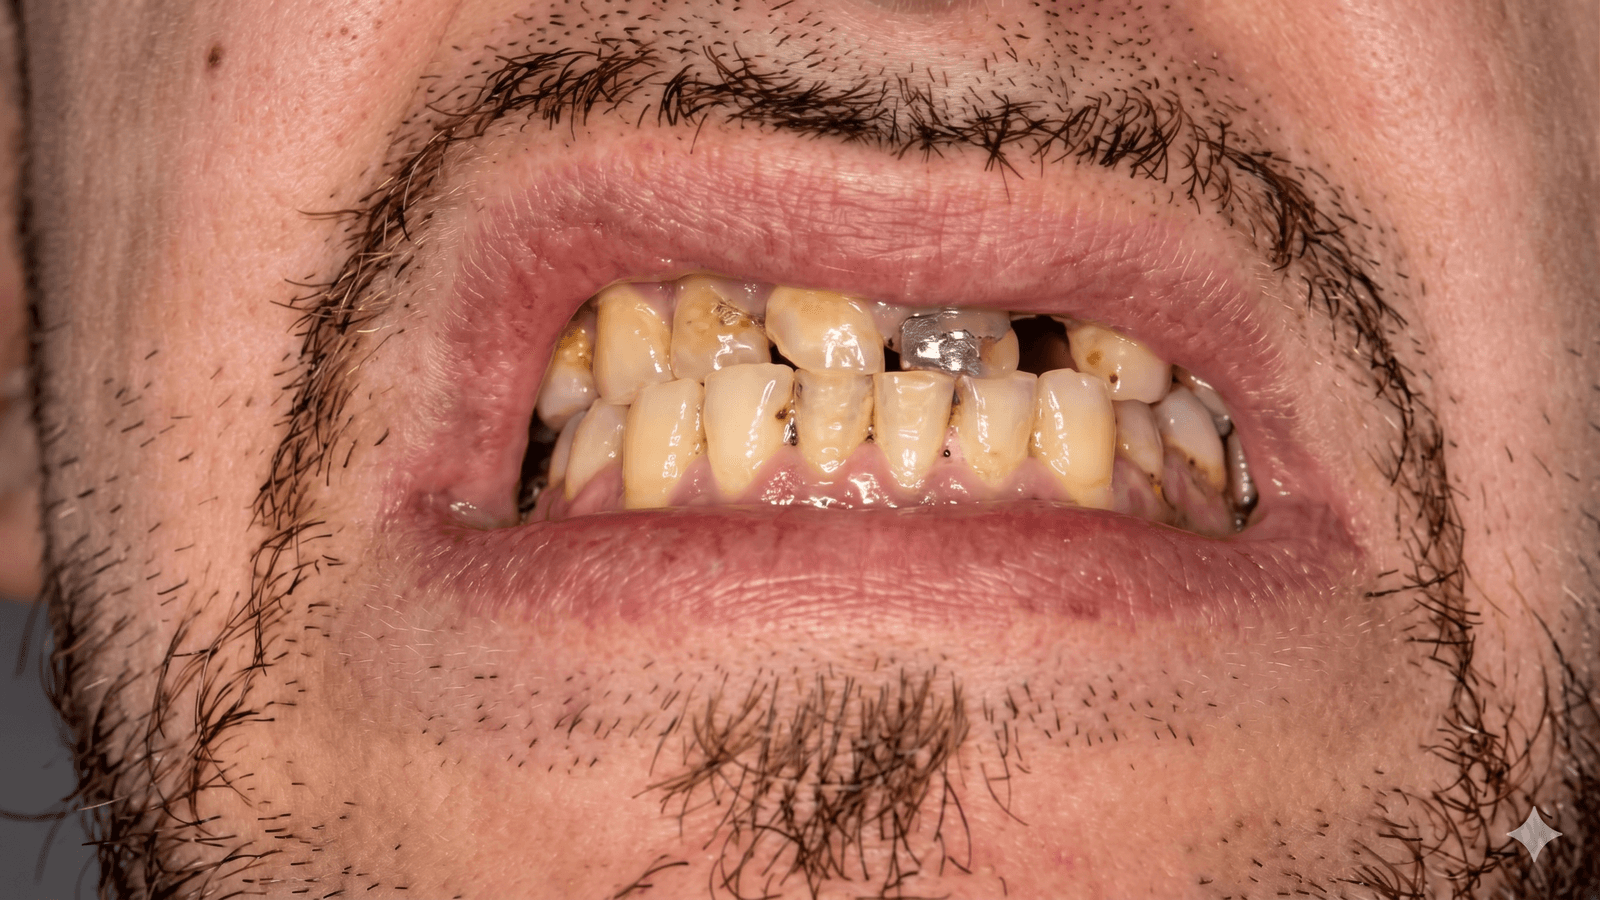

Avevo perso quasi tutti i denti dell'arcata superiore e in Italia mi avevano chiesto 24.000€ per un All-on-6. A Tirana ho fatto lo stesso lavoro a 9.500€, con impianti Nobel Biocare e protesi definitiva in zirconia. Il dentista ha studiato in Germania, parlava italiano, era preparatissimo. Sono passato in due viaggi di 4 giorni e ora mangio di nuovo come prima.

Stefano V.

Padova • Impianti All-on-6